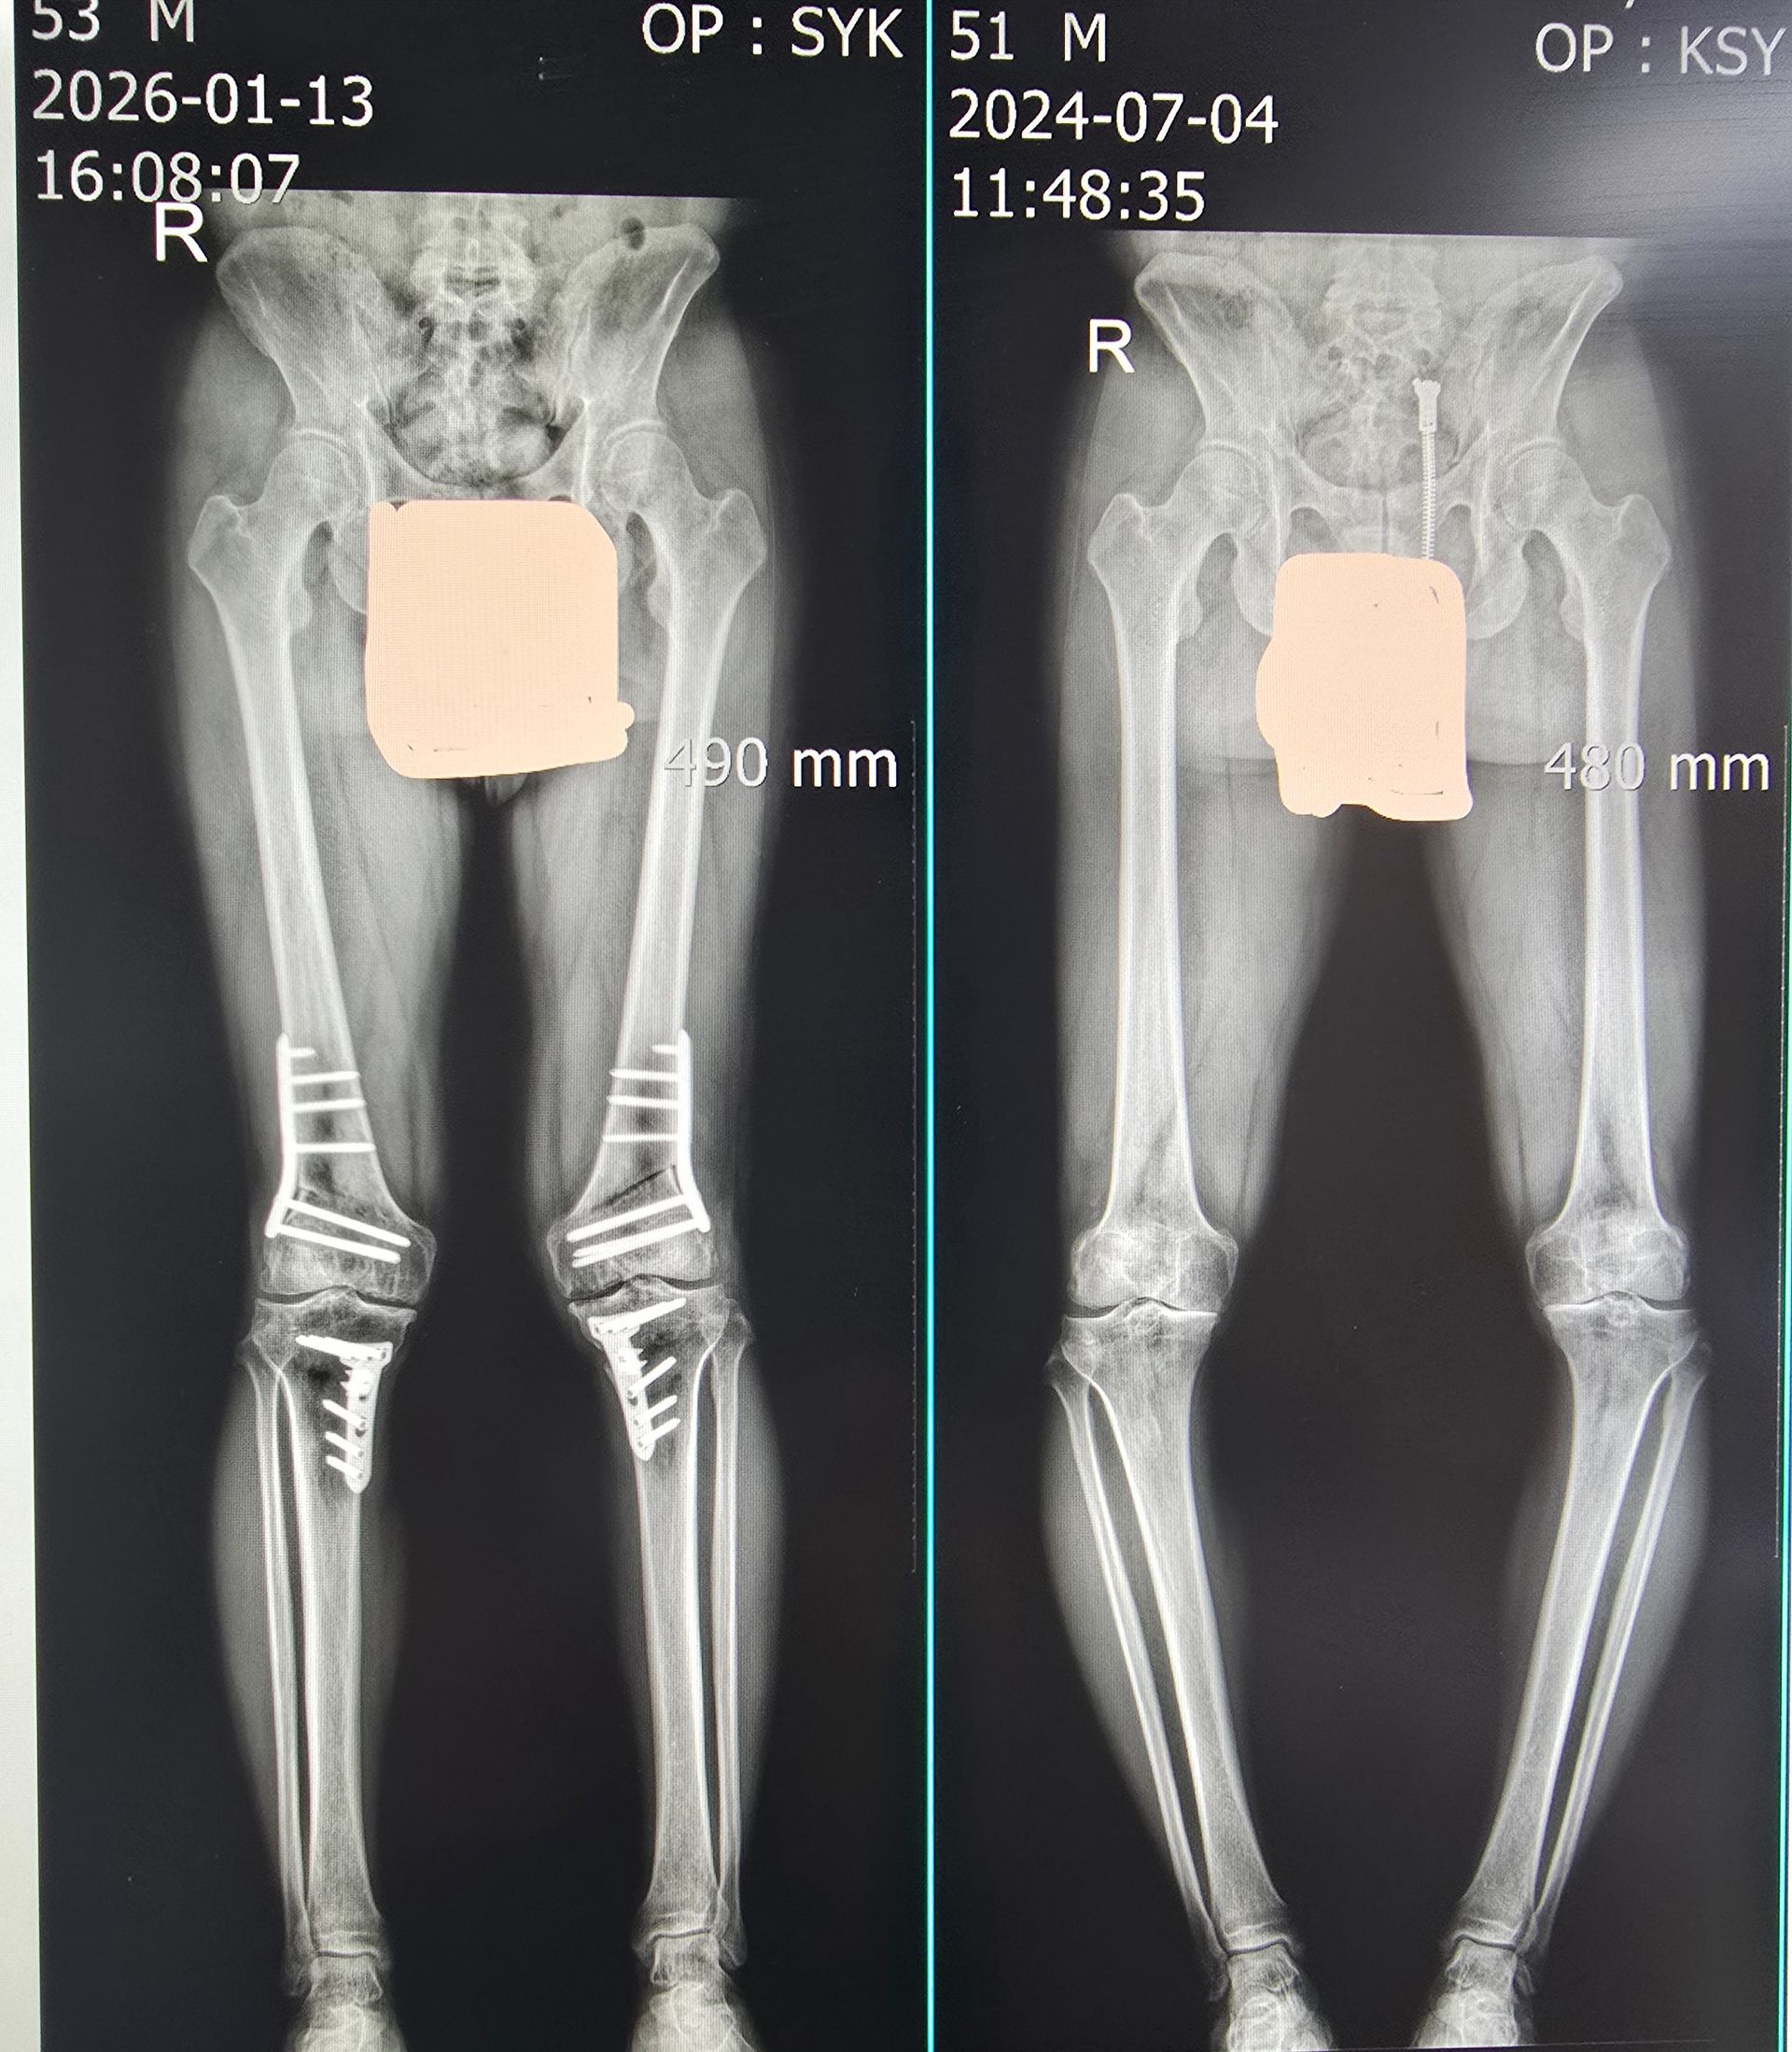

High-Level Osteotomy (HTO / DFO)

- Joint-preserving realignment surgery

- 3D simulation–based planning and precise biomechanical correction

- Structured rehabilitation to extend native joint lifespan

Gangnam JS Hospital is a national leader in cartilage regeneration and joint preservation in Korea. This physician-focused training program delivers hands-on education in stem cell–based cartilage restoration, high-level osteotomy, and advanced arthroscopic surgery, based on protocols that define current orthopedic standards in Korea.

Participants observe and engage in real-world procedures used to repair complex cartilage defects that cannot be adequately treated with conventional methods.

Emphasis is placed on restoring hyaline-like cartilage, optimizing long-term joint function, and minimizing the need for joint replacement.